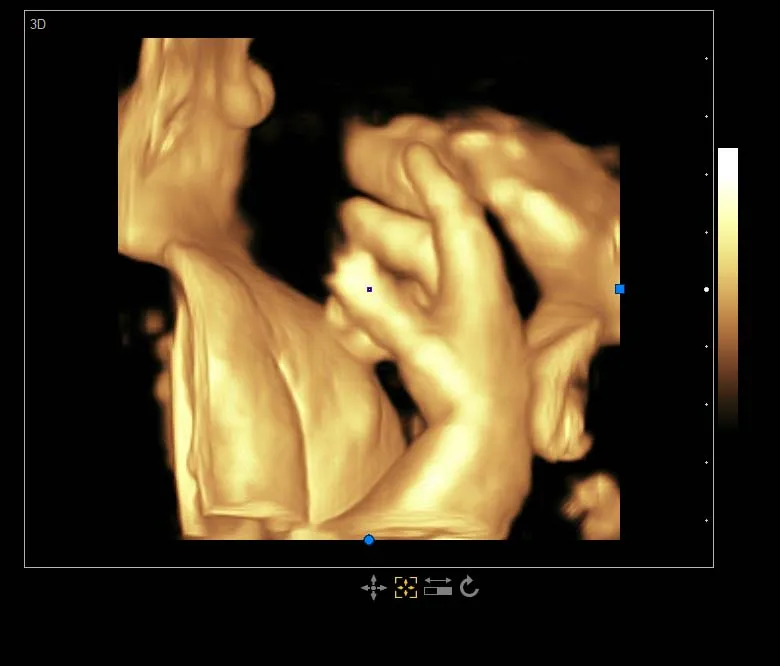

Standard Configuration | Main Unit 3.5Mhz convex probe 4D Volume probe and software 19'LED display with 10.4’ touch screen CW function ( work with phased array probe) USB ports, DICOM 3.0,DVD-RW |

Professional measurement software packages | Obstetric measurement Andrology measurement Gynecological measurement Urology measurement Peripheral vascular measurement Multiple births measurement Small organ measurement Orthopedic measurement Cardiac measurement |